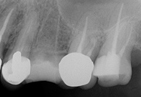

植牙主要是以鈦合金製成的人工植體,來取代原本的牙根,必須透過專業醫師的技術及經驗,精準的將植體植入無牙區域的骨頭內。

一般前牙的植牙價格相對而言會比後牙的植牙價格來得高,因為前牙有美觀上的考量,常常需要用到一

些美學上比較講究的套件,而且前牙最常需要一些補骨或軟組織處理手術的部位,所以一般來說植前排

牙的價格會比植後排牙的植牙價格要來的高。